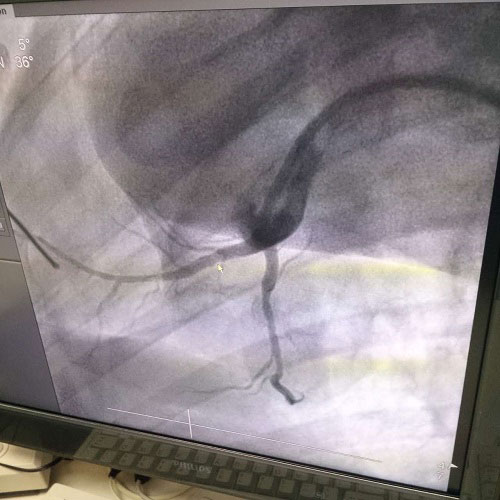

��һ�����V�Ͻ�ˎ��֧�����M������A��

��������S���F���t�����g�İlչ���t���O�����څ���ƣ�������֧���ί��ѽ��ɞ������Ѫ�ܯ�����һ�N��Ҫ�ֶΡ�Ѫ�ܽ��뼼�g�����t�WӰ���O��Č����£����ô���ᘡ����z�����ܵ���е��Ѫ��;���M���\���c�ί��IJ������g���ѽ��ɞ��ί����NΣ�U�������������ѷ���֮һ��

Ŀǰ���R���ϑ��õ�֧�ܷNܶ࣬����֧�ܵIJ��|���鲻�P䓡��-⁺Ͻ���-�t�Ͻ�Ƚ��٣��@Щ����֧�ܶ���������Եģ�����������Ĥ�������װY�����ȡ����Q���y����֧�ܵľ����ԣ����ÿɽ���Ѫ��֧�ܿ��Ժܺõؽ�Q���y����֧�ܴ��ڵ��������}���V�Ͻ�������m�˵����W���ܡ��M�������ԡ�����˨�ԡ������Եȃ��c���ɞ�ɽ���֧�ܵă��x���ϡ�

����ȫ�����V�Ͻ�ˎ��ϴÓ֧�������ɹ�˾��������аl����Ҫ��ˇ���g��ȫ������������ȫ����֪�R�a�ࡣ���ҿ����ԏ���ǰ���аl���A�������Ј��������У���ʩ�L�U�ɿأ���ȫ��ͬ�ИI�I�ȼ��g�����a���ȼ��g�lչ�հף����χ��Үa�I�lչ���ߣ����������Ч���Ŀǰ�V�Ͻ�ˎ��֧�����M������A�Σ�ֲ������w��һ����֮��Ч�����á�